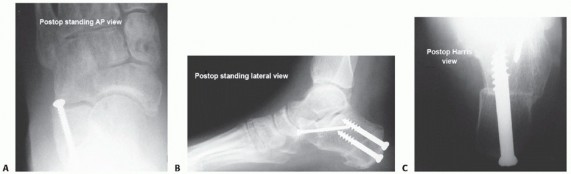

At 2 weeks after the date of surgery, the sutures are removed and simulated weight-bearing radiographs (AP, lateral, oblique, and Harris axial heel views) are obtained (FIG 7).

FIG 7 • A-C. Postoperative standing AP foot, lateral foot, and Harris view of the os calcis. (continued)*